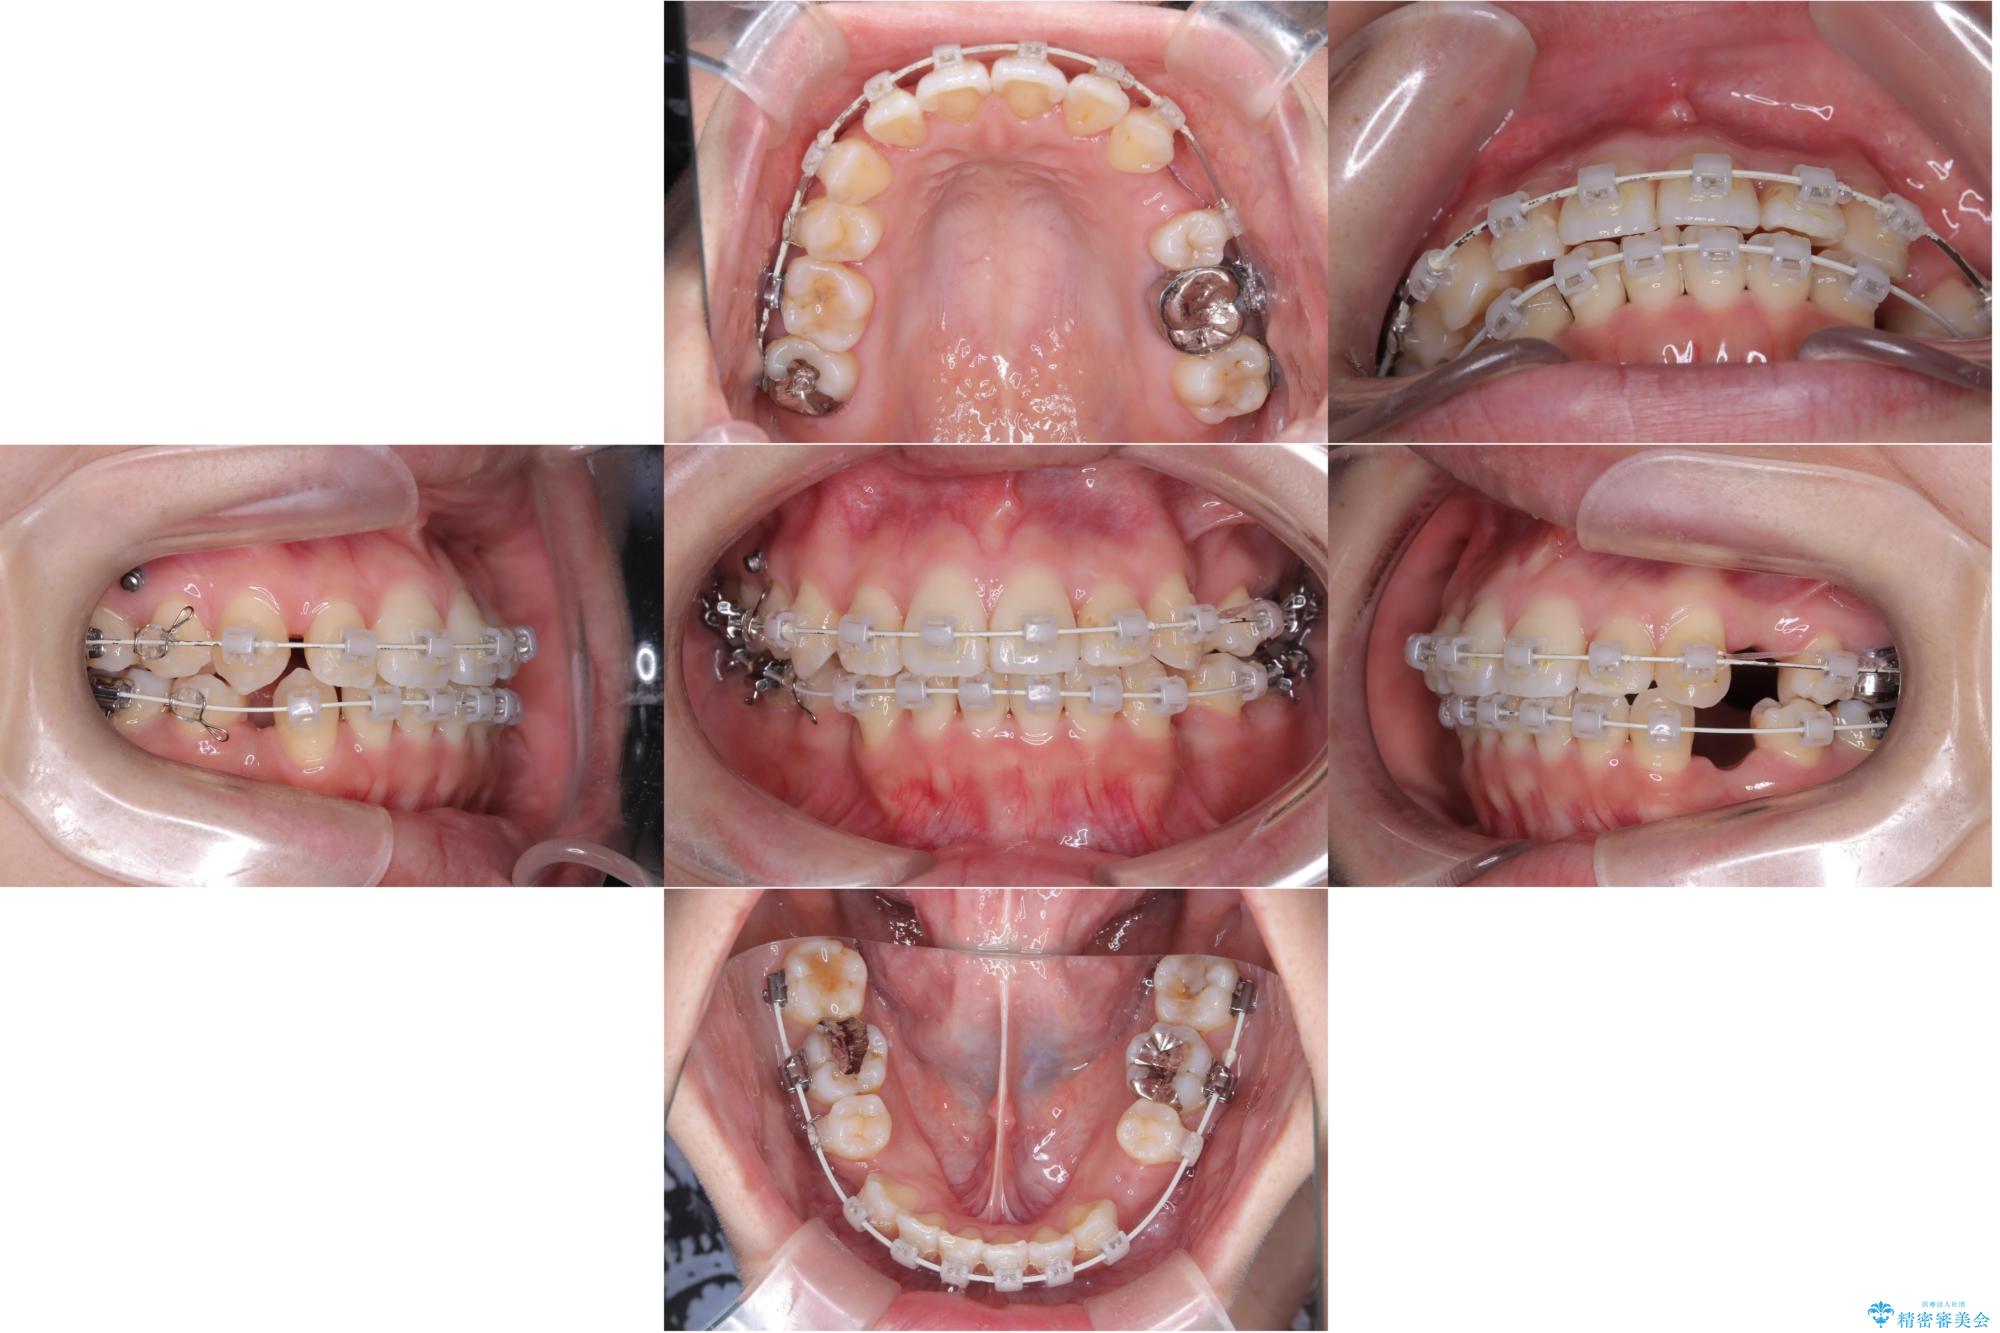

- 主訴:口元を下げて前突感を無くしたい、下の歯の凹凸も無くしたい

右側第二小臼歯、左側第一小臼歯、下顎両側第一大臼歯を抜歯しワイヤ-矯正を行いました。

骨格的顎の変位を認めたため、顔貌に対しピッタリ上下の歯の正中を合わせることは難しいと説明し、上下左右計4本小臼歯を抜歯しワイヤー矯正治療を行いました。

期間:3年